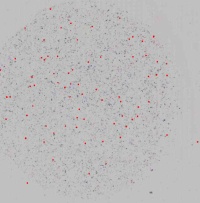

图1

图2

图3

图4

图5

图6

图7

图8